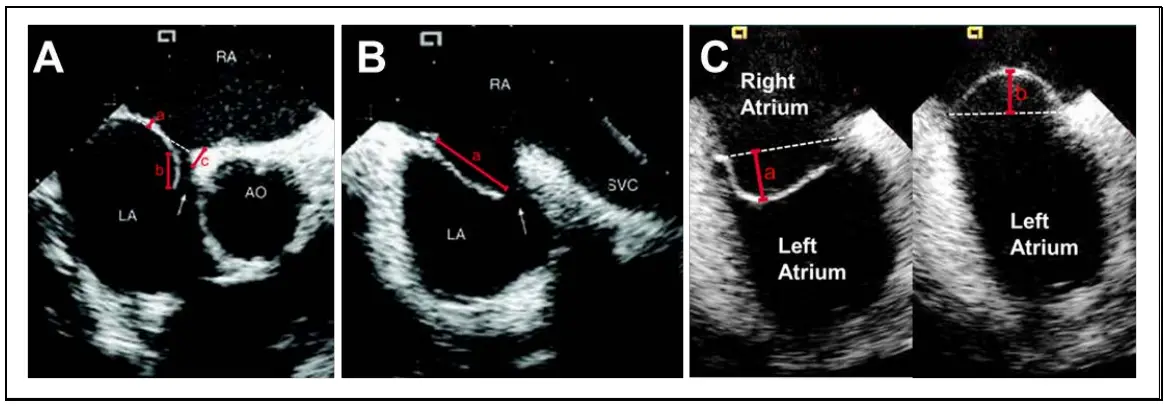

NOTE: PFO morphology is best assessed using a short axis view, where the PFO is visualized adjacent to the aortic valve, and the septum primum is oriented in a near horizontal position (ICE septal short-axis view; TEE angles 30°, 45°, and 60°). Using this view, the excursion of the septum primum, length of the PFO tunnel, and the thickness of the septum secundum are assessed. These features should also be assessed using a long axis bicaval view (ICE septal bicaval view; TEE angles 90°, 105°, and 120° — see Figure 9 and Figure 10).

Figure 9. ICE Images

9A PFO as assessed by ICE in short axis view with measurement of septum primum excursion (a), PFO tunnel length (b), and septum secundum thickness (c). 9B PFO as assessed by ICE in long axis bicaval/SVC view with measurement of septum primum length (a). 9C PFO as assessed by ICE in septal view with measurement of septum primum excursion into left atrium (a) and right atrium (b). Figure 10. TEE Images

10A Measurement of septum primum excursion (a), PFO tunnel length (b), and septum secundum thickness (c) in the short axis 50-degree view (range 30 to 60 degrees to visualize the aortic root en face). 10B Distance from the PFO to aortic root (a) in the 30-degree view (range 0 to 45 degrees to visualize the aortic root en face) 10C Distance from the PFO to the orifice of the superior vena cava (SVC) (a) in the bicaval 90-degree view (range 80 to 125 degrees to minimize foreshortening of the SVC). NOTE: If Imaging cannot clearly localize the PFO, place a wire through the PFO to help with identification.